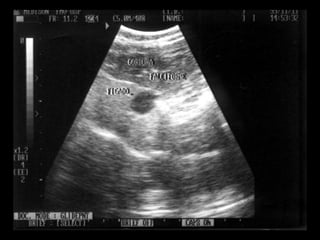

 US: hiperecogenicidade difusa

   US: dilatação de vias biliares, vv portas

   O ultra-som é o melhor método de

distinção entre doença intra-hepática

e obstrução pós-hepática.

Lipidose Hepática Felina examescomplementares:  FA (2-4x), ALT, GGT normal (±80%),  GGT: colangiohepatite associada  BT (75%)  poiquilocitose/ corpúsculos Heinz  hipocalemia (30%) / hipofosfatemia   US: hiperecogenicidade difusa

Colangite neutrofílica (aguda)  curso da doença < 5 dias  gato macho, magro, jovem-meia idade  anorexia, letargia, emese, febre, hepatomegalia, dor abdominal  Lab: GGT & ALT, BT & FA  US: dilatação de vias biliares, vv portas evidentes, ecotextura irregular (grosseira ou nodular)